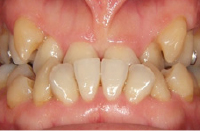

治療前